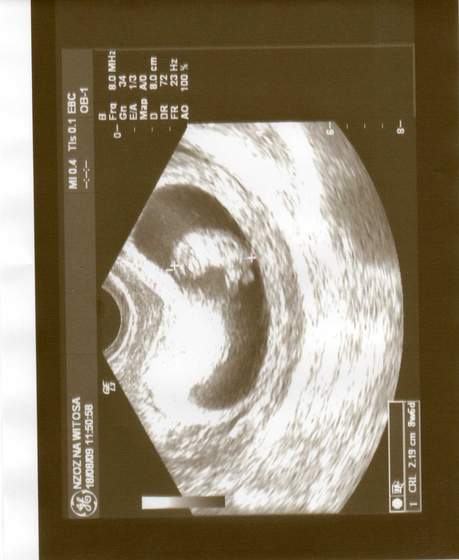

:-)a to moj maly łobuz... no w sumie nie taki maly bo chyba przez to ze wciagnal braciszka to ma az 7,7 cm;-) szkoda ze drugiego juz nie ma